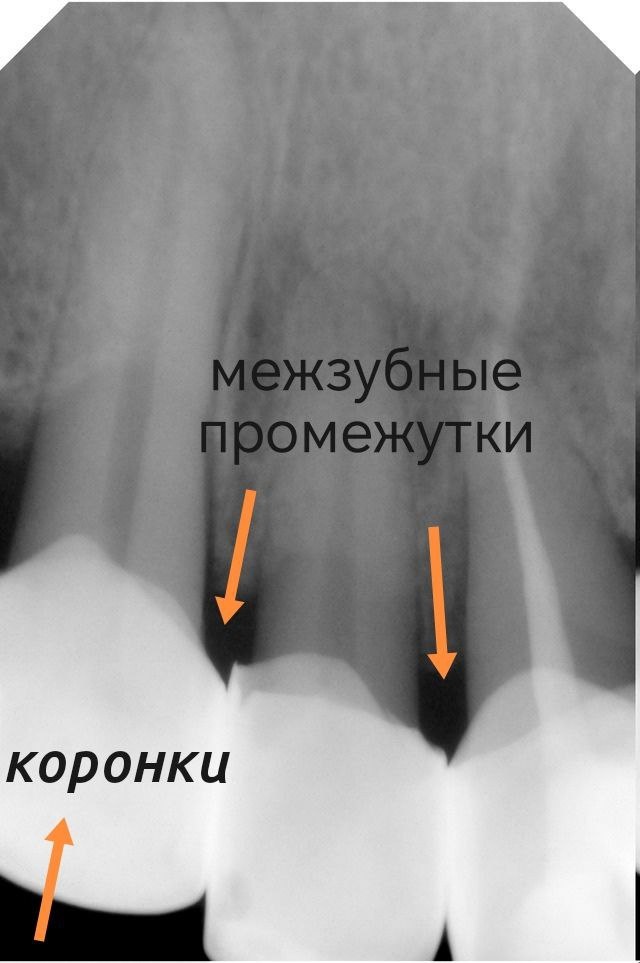

Межзубные промежутки — это место, куда щётка просто не залезает.

Щетинка физически не может очистить пространство "между" зубами. А там скапливается всё самое “интересное”: мягкий налёт, остатки еды и то, что потом превращается в запах и воспаление.